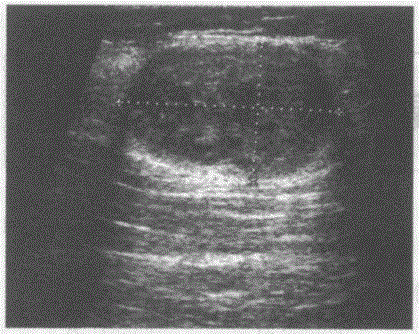

问题 临床资料:男,32岁,自诉左肘部触及一肿物数月余。 超声综合描述:左肘部可见8.7cm×5.7cm椭圆形不均质中等回声,边界清晰,形态规则,与神经走行关系密切。 超声提示:

选项 A.左肘内侧神经鞘瘤 B.左肘内侧纤维瘤 C.左肘内侧血肿 D.左肘内侧表皮样囊肿

答案 A